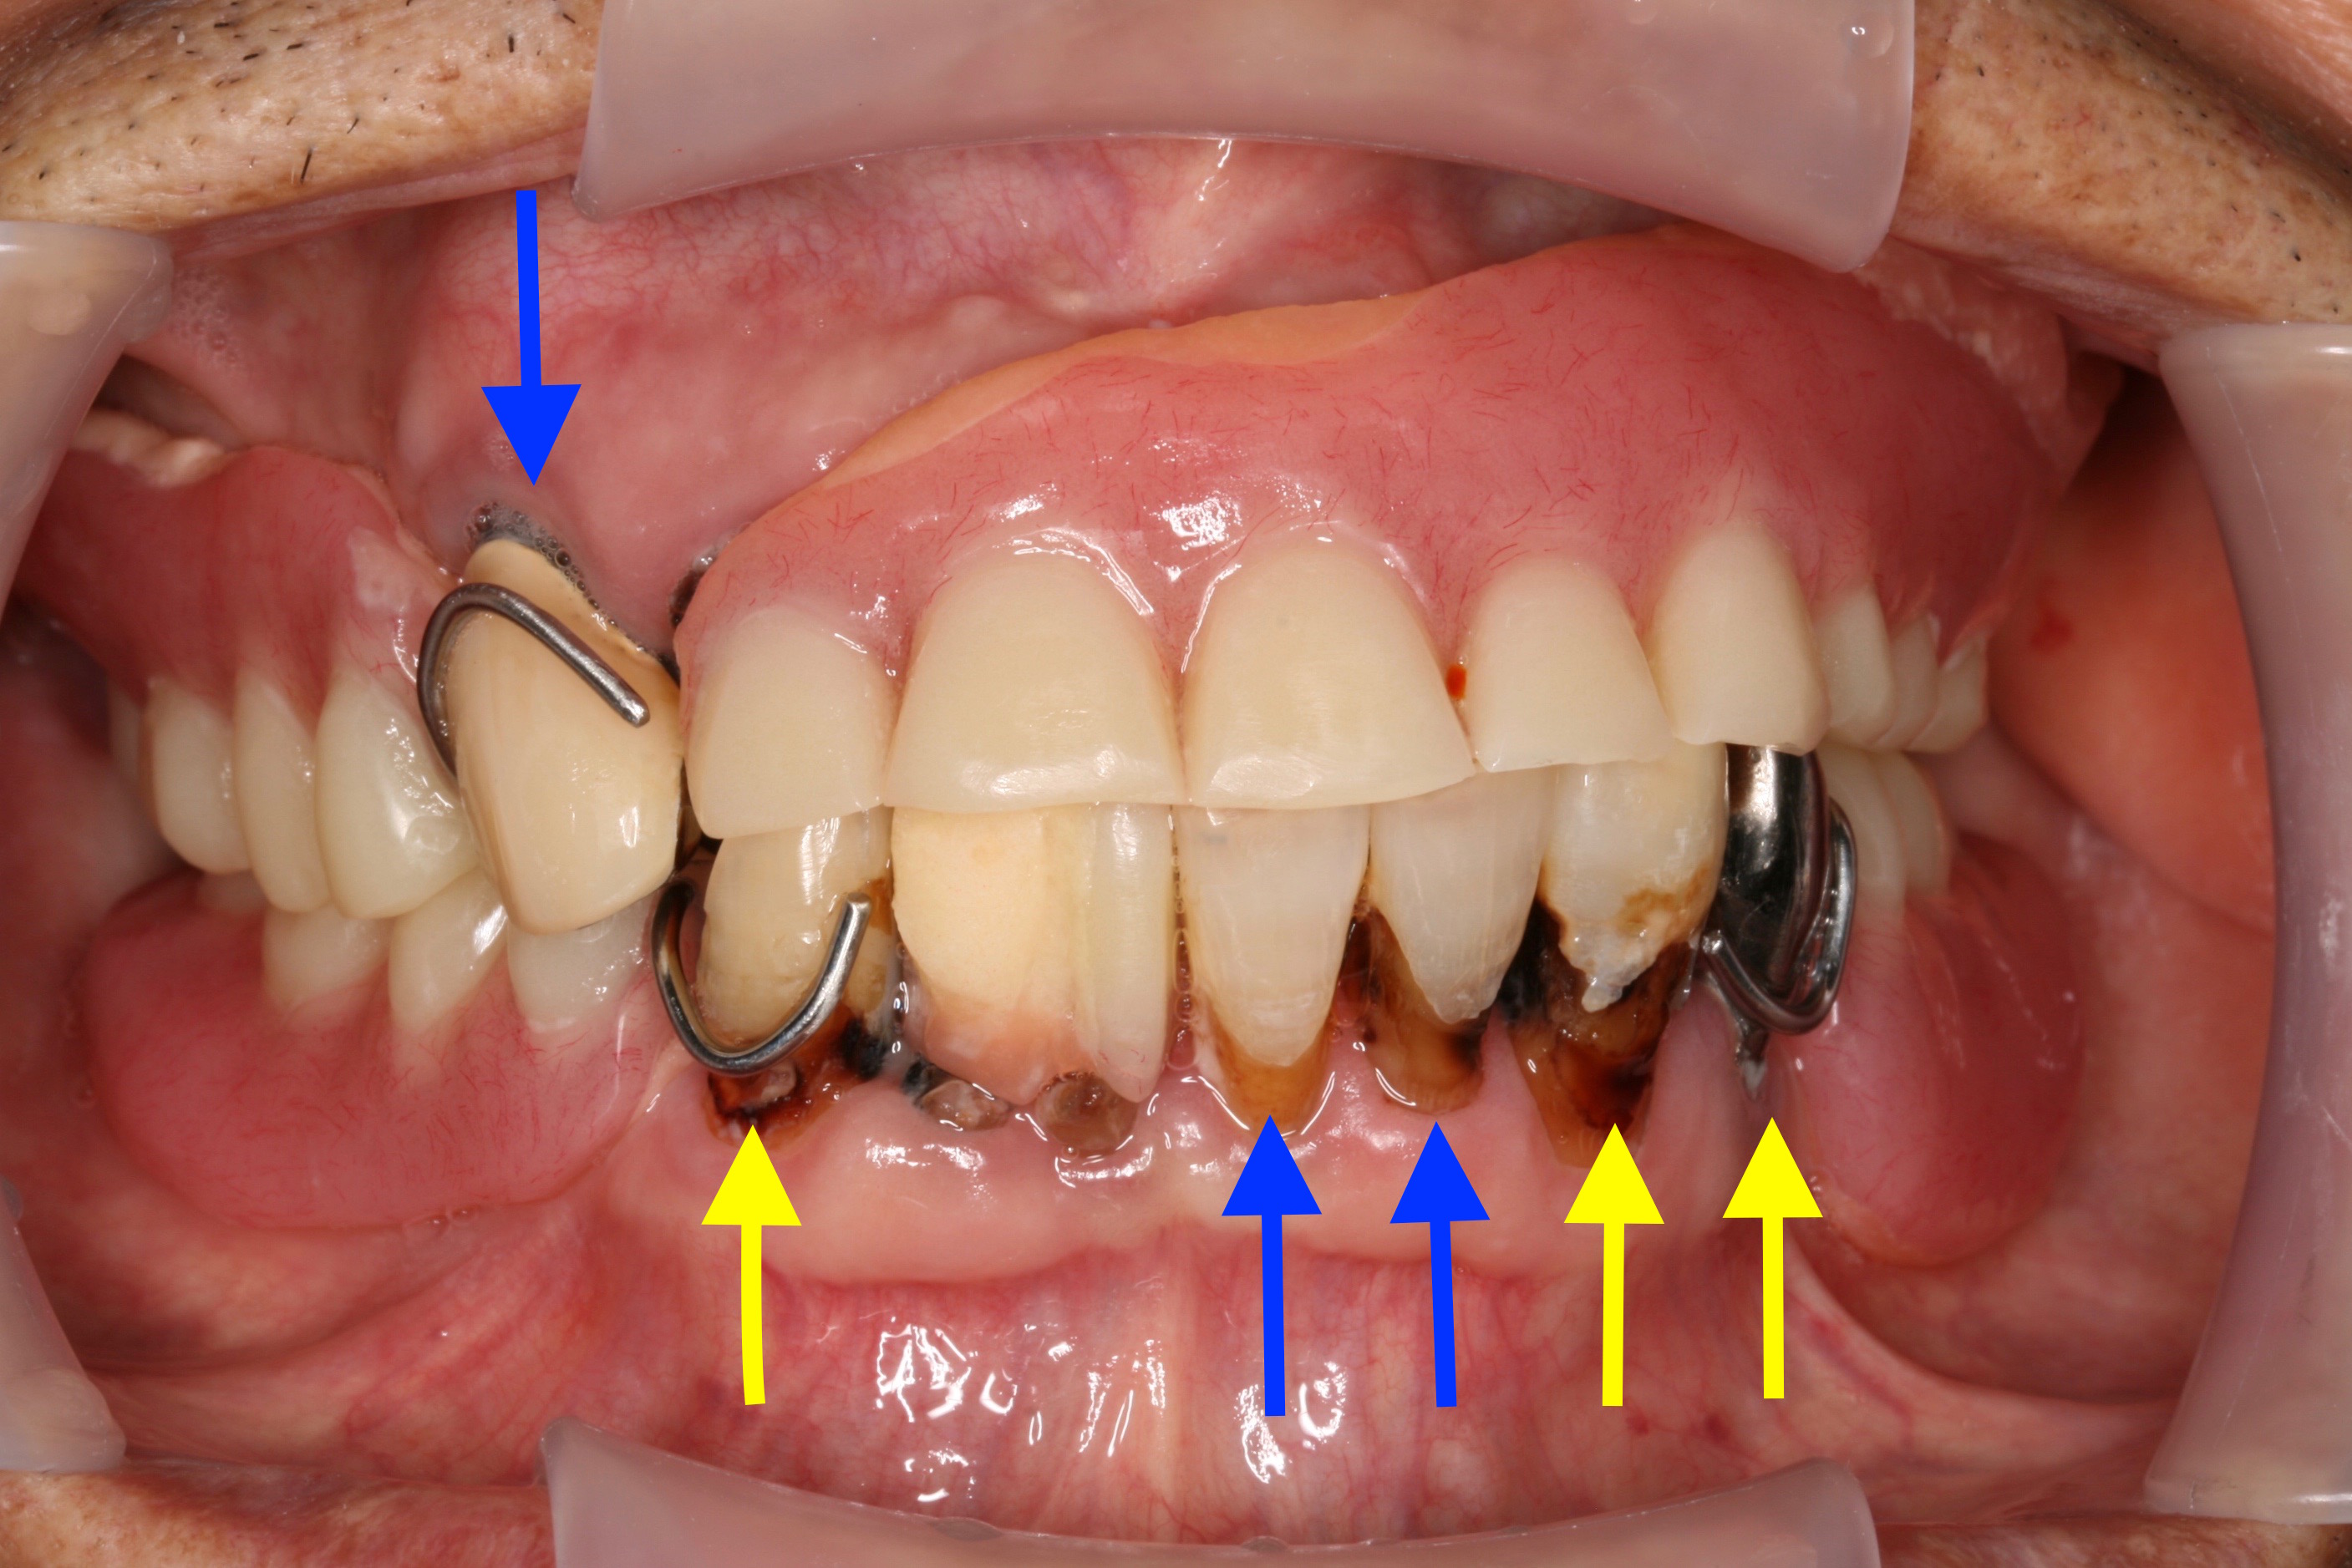

ケース NO.2 ⬆︎ 残した歯 ⬆︎ 抜いた歯

上がレジリエンツテレスコープ義歯、下が総入れ歯

この患者様は下アゴが分からない程痩せてしまっているため、

高度な技術が必要となります。